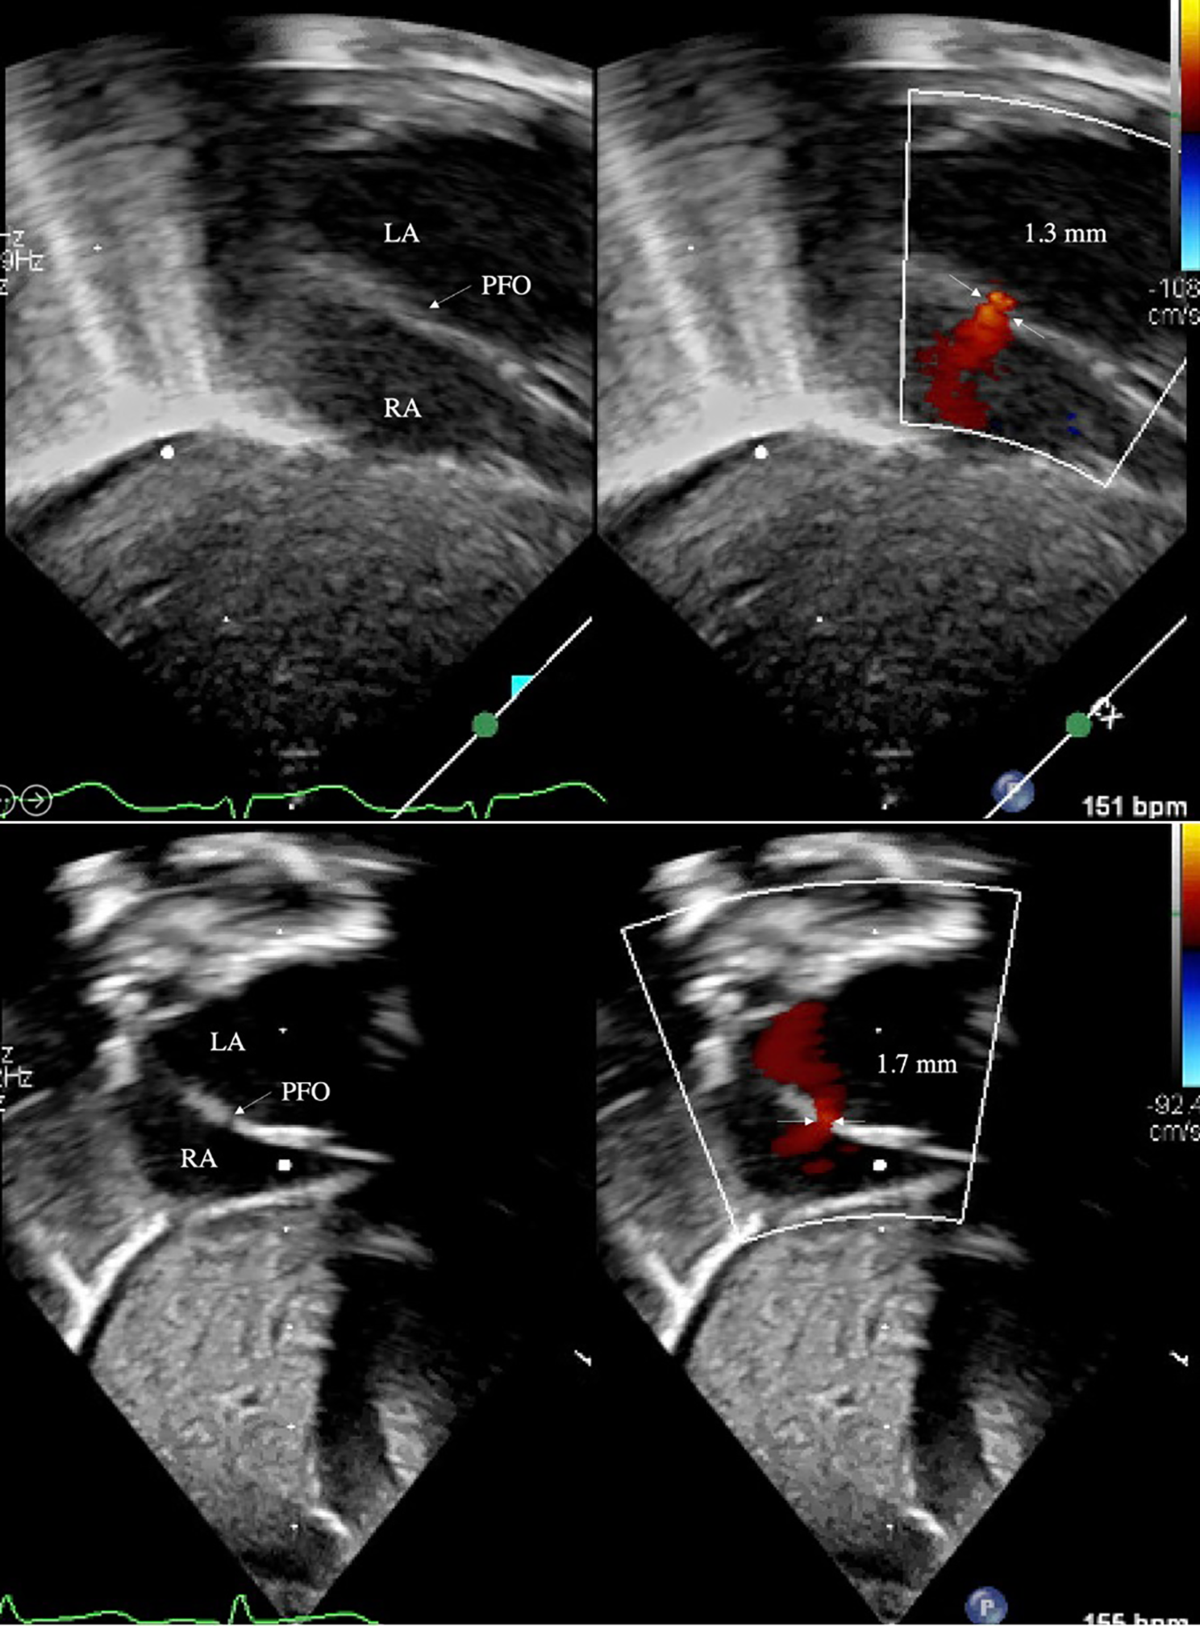

pfo in infants sale